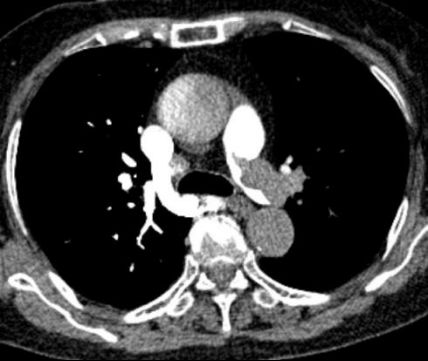

急診醫(yī)生快速研判,高度懷疑為急性肺栓塞。肺動脈CTA檢查結果證實了判斷:雙側肺動脈主干及分支存在多處血栓栓塞,右心室明顯擴大——這是急性肺栓塞的典型征象,說明肺動脈堵塞已導致右心室負荷急劇增加,心臟功能受損。

圖:胸部增強CT(CTPA)示右肺動脈主干及分支內可見多發(fā)充盈缺損提示肺動脈栓塞